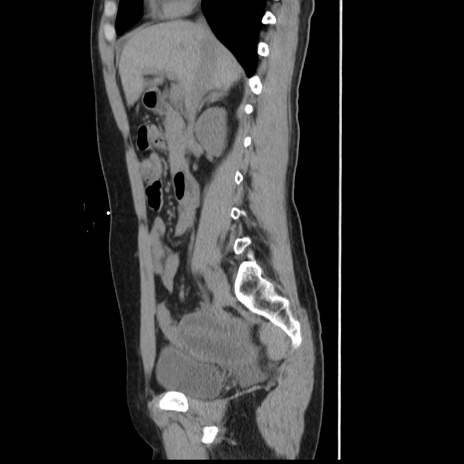

横断像

【症例】 50歳代女性

【主訴】 腹痛

【現病歴】前日生レバーを食べた。今朝に排便あり。 昼前に突然発症の腹痛を生じ、当院救急外来を受診した。

【既往歴】 子宮筋腫にてで子宮全摘後

【身体所見】 意識清明、腹部:平坦、軟、下腹部やや左を中心に圧痛・反跳痛あり、筋性防御あり

【データ】WBC 7800、CRP 0.07